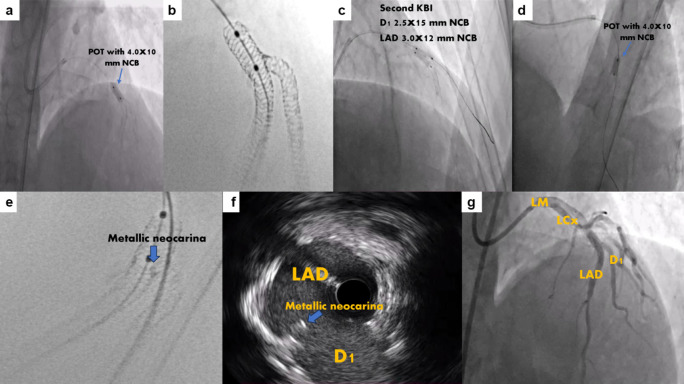

A Novel Modified Mini-Crush Technique for Complex Coronary Bifurcation Lesions: Controlled Balloon-Crush